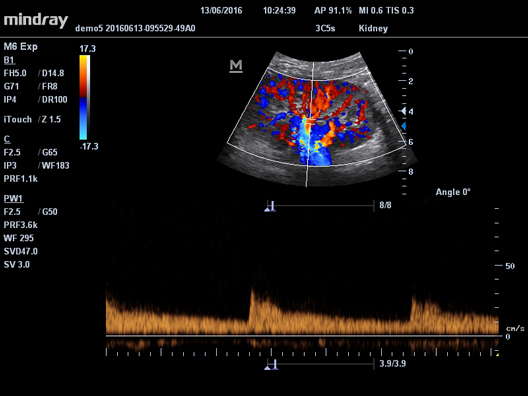

HR Flow

Передовая технология на основе эксклюзивного алгоритма обработки изображений Mindray, обеспечивающая улучшенную визуализацию мельчайших сосудов и сложных структур потока.

Галерея изображений